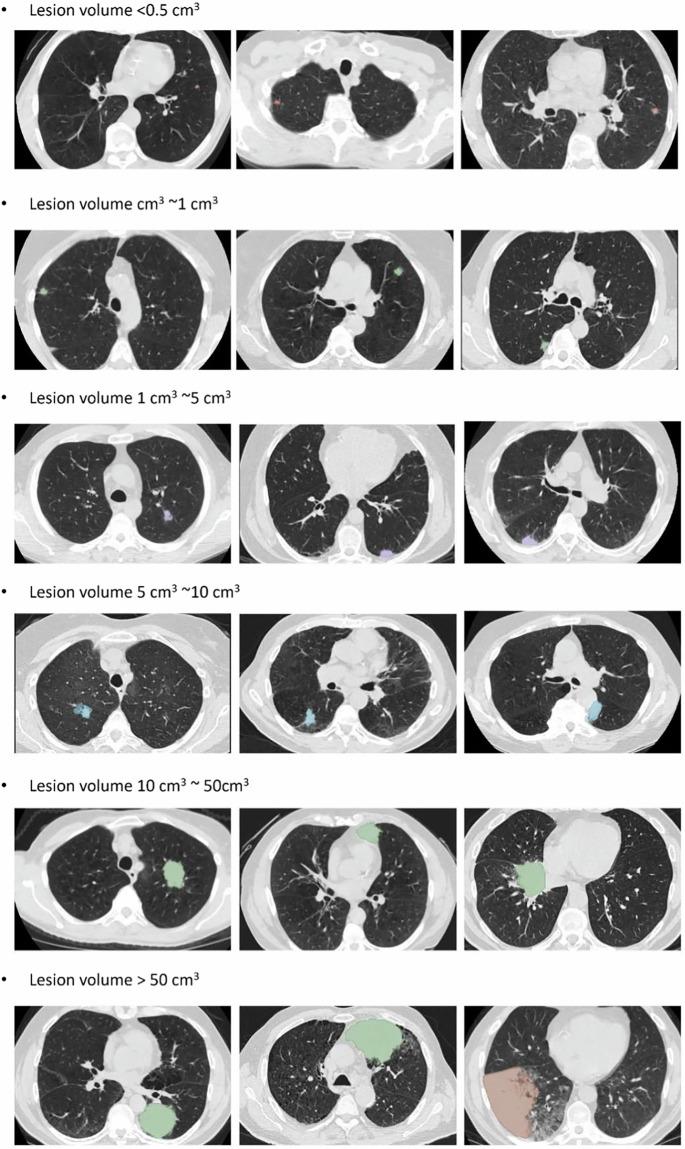

Low-dose computed tomography (LDCT) is the most effective tools for early detection of lung cancer. With advancements in artificial intelligence, various Computer-Aided Diagnosis (CAD) systems are now supported in clinical practice. For radiologists dealing with a huge volume of CT scans, CAD systems are helpful. However, the development of these systems depends on precisely annotated datasets, which are currently limited. Although several lung imaging datasets exist, there is only few of publicly available datasets with segmentation annotations on LDCT images. To address this problem, we developed a dataset based on NLST LDCT images with pixel-level annotations of lung lesions. The dataset includes LDCT scans from 605 patients and 715 annotated lesions, including 662 lung tumors and 53 lung nodules. Lesion volumes range from 0.03 cm to 372.21 cm, with 500 lesions smaller than 5 cm, mostly located in the right upper lung. A 2D U-Net model trained on the dataset achieved a 0.95 IoU on training dataset. This dataset enhances the diversity and usability of lung cancer annotation resources.

低剂量计算机断层扫描(LDCT)是早期检测肺癌最有效的工具。随着人工智能的发展,目前临床实践中支持各种计算机辅助诊断(CAD)系统。对于处理大量CT扫描的放射科医生来说,CAD系统很有帮助。然而,这些系统的开发依赖于精确标注的数据集,而目前此类数据集有限。尽管存在几个肺部影像数据集,但只有少数公开可用的LDCT图像分割标注数据集。为了解决这个问题,我们基于NLST LDCT图像开发了一个具有肺部病变像素级标注的数据集。该数据集包括来自605名患者的LDCT扫描和715个标注病变,其中包括662个肺肿瘤和53个肺结节。病变体积范围从0.03立方厘米到372.21立方厘米,500个病变小于5立方厘米,大多位于右上肺。在该数据集上训练的二维U-Net模型在训练数据集上实现了0.95的交并比。这个数据集增强了肺癌标注资源的多样性和可用性。